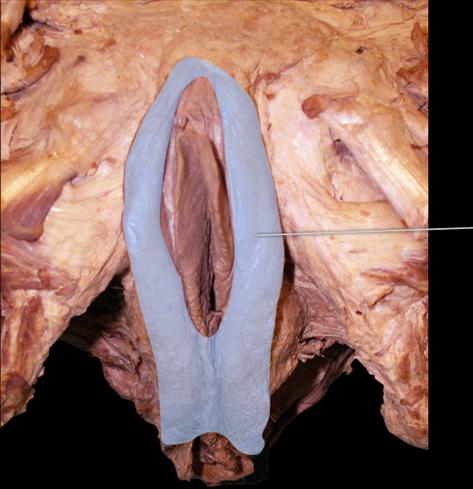

Identify the highlighted tissue in the vaginal wall.

Stratified Squamous Epithelium

Identify the highlighted structures.

Labia Majora

Identify the highlighted structure.

Vagina